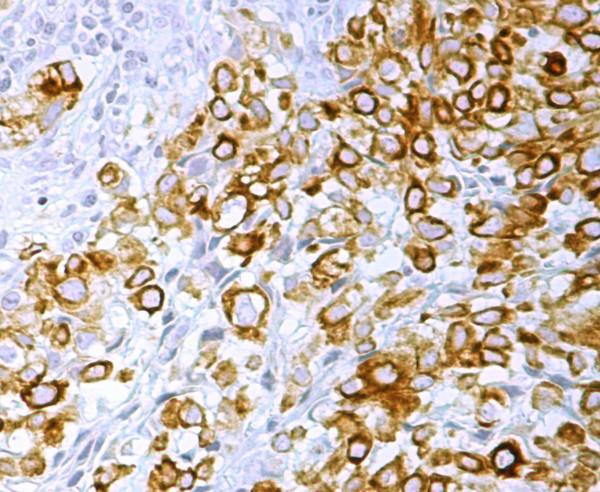

CASE PRESENTATION

We present an unusual case of CCSTA overlying the scapular region and with secondary osseous extension in the lower scapula. The patient underwent a wide local excision with removal of the tumor and the lower two thirds of the scapula. He had no local recurrences but he developed lung metastases after 5 months in spite of postoperative chemotherapy. He finally died ten months later.

病例报告

我们报告一例罕见的CCSTA病例,肿瘤位于肩胛区域并继发于肩胛骨下部骨质浸润。患者接受了广泛的局部切除,切除了肿瘤及肩胛骨下三分之二。患者无局部复发,但尽管术后进行了化疗,5个月后仍出现肺转移。10个月后患者最终死亡。